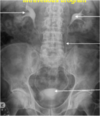

What can you see in this abdominal X-ray?

Staghorn calculus in left kidney.